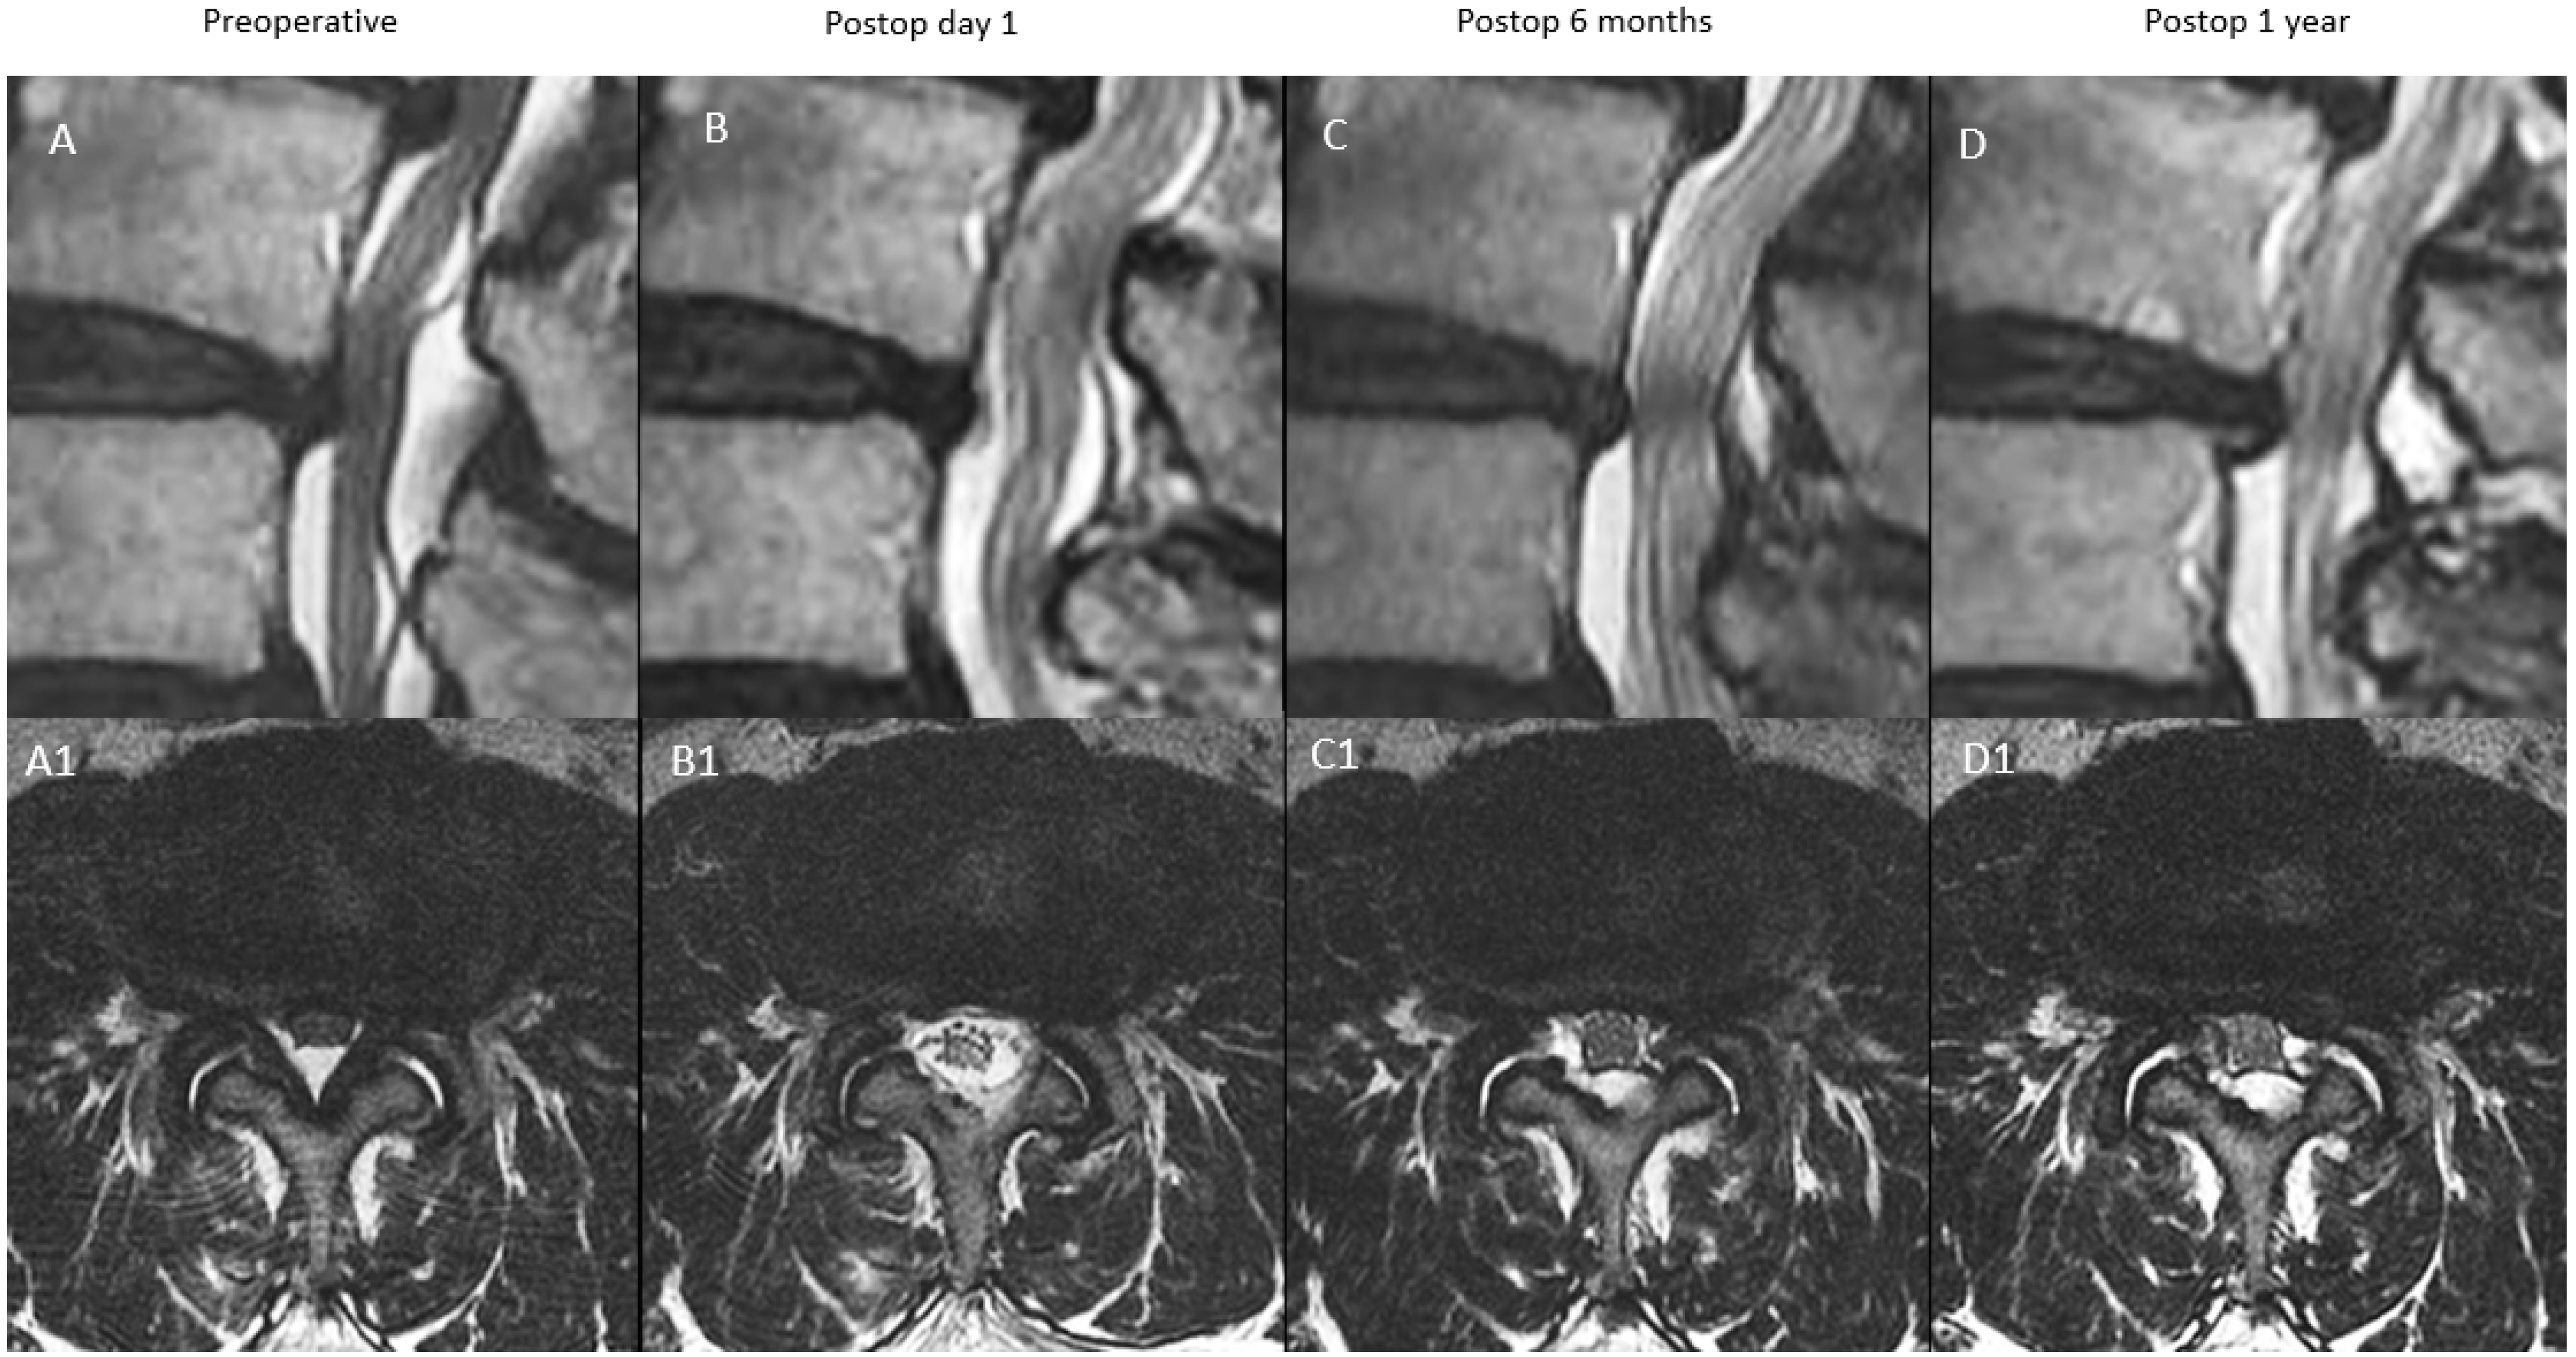

| A: Continuous Type | There is significant decompression with increased spinal canal area on postoperative day one, a modest drop at postoperative 6 months and close to postoperative 6 months value at postoperative one year | X | ≥70% X | 70–90% X (close to postoperative six months value) |

| B: Remodelling Type | There is significant decompression with increased spinal canal area on postoperative day one, a significant drop at postoperative 6 months and modest improvement at one year but less than 90% of the postoperative day one spinal canal area | X | <70% X | 70–90% X |

| C: Expansion Type | There is significant decompression with increased spinal canal area on postoperative day one, a modest drop at postoperative 6 months and significant improvement at one year with more than 90% of the postoperative day one spinal canal area | X | ≥70% X | 90–100% X |

| D: Restenosis Type | There is significant decompression with increased spinal canal area on postoperative day one, a significant drop at postoperative 6 months and minimal improvement at one year with <70% of the postoperative day one spinal canal area | X | <70% X | <70% X |